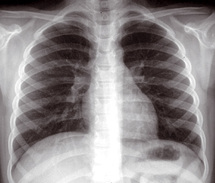

Cette réalité vient d’être rappelée à l’occasion de la Journée mondiale contre la tuberculose célébrée hier sous le thème « Chacun de nous a un rôle à jouer dans la lutte antituberculeuse». Selon un communiqué du ministère de la Santé rendu public à cette occasion, c’est dans les zones les plus urbanisées et en l’occurrence les plus peuplées, particulièrement dans les grandes villes que 70% des nouveaux cas de tuberculose ont été dépistés. L’analyse par sexe montre par ailleurs que cette maladie touche plus les hommes (57% des cas), que les femmes (43%). Aucune indication n’a été donnée en ce qui concerne le milieu social, mais il va sans dire que la tuberculose évolue dans les milieux les plus pauvres et de surcroît les moins sains.

Considérés comme un problème de santé publique, les malades tuberculeux sont pris en charge gratuitement dans les centres spécialisés de diagnostic de la tuberculose du ministère de la Santé. Les médicaments antituberculeux y sont, de ce fait, distribués à titre gracieux sous contrôle médical dans les 2600 centres de santé urbains et ruraux. Ces derniers y sont suivis tout le long de la durée du traitement qui peut varier de 6 à 18 mois, selon la nature de la maladie et sa localisation.

Un traitement bien suivi donne des résultats probants et permet une guérison complète. En revanche, c’est l’interruption volontaire du traitement qui semble poser un sérieux problème dans la lutte contre la tuberculose. Selon le ministère de la Santé, Ces malades qui interrompent leur traitement s’exposent au risque de la multi-résistance du bacille de la tuberculose aux traitements disponibles et leur prise en charge se trouve plus compliquée et plus longue.

Afin de lutter contre cette maladie, ce département a mis en place une stratégie s’étendant entre 2008 et 2012. Elle vise à terme la réduction de son taux d’incidence, à 65 nouveaux cas pour 100.000 habitants contre 85 nouveaux cas pour 100.000 en 2008.

Pour ce faire, il propose d’agir à travers différents axes dont le renforcement du dispositif de prise en charge des malades tuberculeux, notamment par la création de deux pôles d’excellence à Rabat et à Casablanca pour la prise en charge des malades multi-résistants, la lutte contre la tuberculose multi-résistante, la co-infection tuberculose/VIH et l’amélioration de la prise en charge de la tuberculose dans les institutions carcérales, la délocalisation des activités du programme national de lutte antituberculeuse vers les régions en vue de plus d’adaptabilité et d’efficience des actions et surtout le maintien de la vaccination au BCG dans le cadre du Programme national d’immunisation.

Dans le monde, la situation est loin d’être reluisante. Selon l’Organisation mondiale de la santé, près du tiers de la population mondiale est infecté par le bacille de la tuberculose, soit 2 milliards d'individus dont plus de 8 millions de nouveaux cas enregistrés chaque année. La maladie est même devenue l’une des principales causes de décès chez les personnes vivant avec le virus du SIDA, avec près de 200.000 décès annuellement.